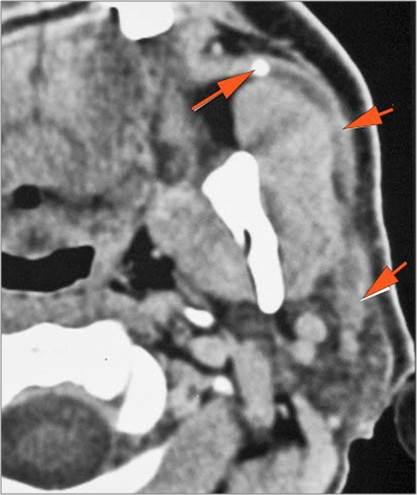

There is edema within the adjacent deep neck, retropharyngeal and/or prevertebral spaces

There is abscess within the adjacent deep neck, retropharyngeal and/or prevertebral spaces.